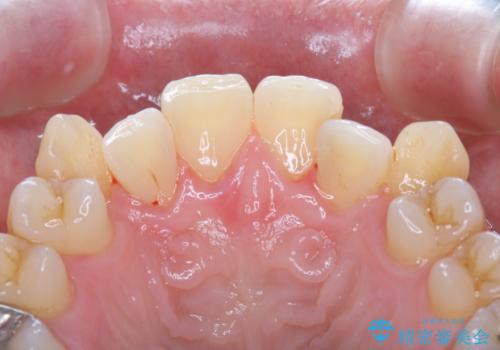

[エアフロー] スプレーの噴射によりしつこい色素沈着やプラークを除去

エアフローによるクリーニング